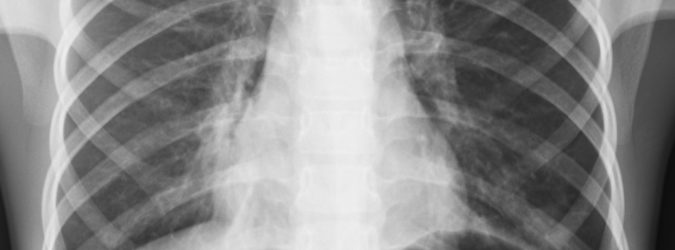

Non stupisce la decisione degli ospedali e dei centri per la sanità delle Marche che hanno destinato, proprio nell’ultimo periodo, un numero cospicuo di fondi dedicati all’acquisto di apparecchi per la TAC accurati e veloci. Se fino a poco tempo fa la radiologia era impiegata esclusivamente nello scansionare ampie parti del corpo, come il torace o il bacino, oggi questo tecnologia viene invece utilizzata per monitorare aree più specifiche e dettagliate. Dall’analisi di cervello e scatola cranica si è velocemente passati alla scansione precisissima di organi come gli occhi.